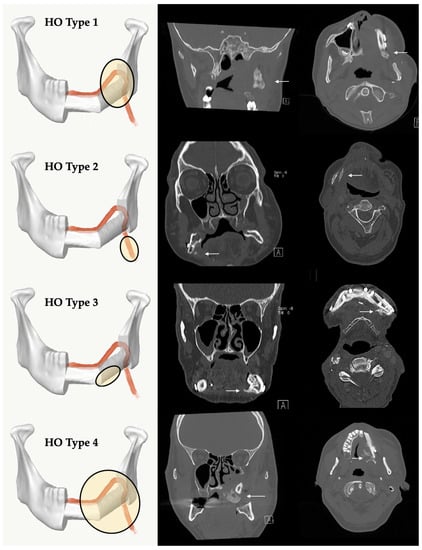

Systematic evaluation of the patient records was performed to identify the cases in which the clinical presence of HO in the vascular pedicle region (palpable submandibular “bone-hard” swelling, ongoing difficulty swallowing and/or the periosteal tissue) led to clinical complications. For the radiological description, five types of HO patterns were defined (Figure 1 and Figure 2): no recognizable ossification of the vascular pedicle or perosseous tissue corresponds to type 0. Type 1 shows an ossification at the transition zone from fibula graft to vascular pedicle. Type 2 shows isolated ossification of the vascular pedicle without contact to the fibula. Type 3 is defined as an isolated HO of periosseous tissue without pedicle-associated ossification. Type 4 is a combination of HO of the vascular bundle and periosseous tissue.

Figure 1. Classification of different radiological types of heterotopic ossification (HO): Type 1 = HO at the transition zone from fibula graft to vascular pedicle, Type 2 = HO isolated at the pedicle without contact to the fibula, Type 3 = HO appears isolated at the periosseous tissue without involvement of the vascular pedicle, Type 4 = a combination with ossification of the pedicle and periosseous tissue. The white arrows mark region of interest. A = Anterior.

Figure 2. 3D-volume rendering of clinical examples of HO Types 1–4. The white arrows mark the regions of interest.

The analysis of the CT-scans showed four different patterns (types) of HO. Distribution and results are shown in Table 2. HO Type 1 was most frequently observed in four cases after maxilla (13.79%) and in 10 cases after mandible (34.48%) reconstruction with FFF. Isolated ossification of the pedicle (Type 2) accounted for seven cases in the mandible (24.14%) and 6.9% (n = 2) in the maxilla. In three cases, combined ossification (Type 4) after maxilla reconstruction (10.34%) and only one case after mandibular reconstruction were recorded. HO Type 3 was only recorded in two cases after mandibular reconstruction (6.9%). Figure 5 illustrates the distribution of HO types according to the number of fibula segments used. A homogeneous distribution of HO Type 1 is shown across all reconstruction localizations and shapes, while Type 2 and Type 4 are found in both types of jaw reconstruction. Type 3 could only be observed after mandibular reconstruction. Figure 6 outlines the appearance of HO in CT scans considering the number of used fibula segments in maxillary or mandible reconstruction. HO occurred more frequently after bi-segmental (33.3%) maxillary reconstruction compared to mono-segmental (29.1%) maxillary reconstruction. In the mandible, HO was most frequently observed after tri-segmental (26%) reconstruction compared to mono-segmental (20%) and bi-segmental (15%) reconstruction.

4.2. Classification of Four Different HO Patterns and Biological Etiology

The HO classification suggested in this study distinguishes four types of HO. Type 1 is the most frequently observed variant across all reconstruction sites and forms. Concerning the referred theories of HO etiology, the bone healing/fracture repair theory describes the origin of HO from the resection site. Functional stress to the stabilized bone graft induces micromotion and enhances bone healing and callus growth [36]. We hypothesize that, as a result, the calcified tissue is a type of excessive bone healing that originates from the resection site and courses along the remaining periosteum at the pedicle by molecular stimulation from osteoprogenitor recruitment [31,42,50].

Type 2 may be the result of isolated periosteal cells in contact with osteocytes along the pedicle from osteo-cutaneous FFF [26,51,52,53]. A long vascular pedicle with remaining periosteal cells therefore offers more potential for the development of HO [25]. We expected that HO Type 2 will be more common, especially in maxillary reconstructions but we found only two cases after maxilla, but seven cases after mandible reconstruction. However, molecular interactions and the influence of BMPs on the induction of wound healing could promote HO formation [31]. Local factors could have additional influence after bone resections.

HO Type 3 was only observed after mandible reconstruction. Its clinical appearance is similar to torus mandibularis. The occurrence of ectopic oral bone formation is probably the result of functional aspects of mastication [54,55]. Thus, this HO type could be triggered by manipulation of the periosteum and its dissection during preparation and maintained by functional factors induced by mastication. In addition, mechanical stress (tension) supports BMP signaling [31]. Keeping this in mind, we expected to find HO Type 3 occurring more frequently in poly-segmental reconstructions close to the resection sites and more particularly at intersegmental graft sites. There are discrepancies between cross sections of resection sites and FFF. Remnant free periosteum after poly-segmental shaping procedure around vascular bundle needs to be considered as an origin of HO. There were no clear reasons why HO Type 3 was not found after maxillary reconstruction. One thinkable hypothesis is that HO Type 3 origin might be an hyperperfused and inflated bone feeder vessel via the above-mentioned mechanisms of blood flow and perfusion theory. For maxillary reconstruction the strong and rigid tissue of the gum might be a sufficient resistance to prevent its development in compare to the more loose and wide tissue of the floor of the mouth.

Changes in blood flow and pressure could also induce HO Type 4 [36]. Three cases after maxilla and one after mandible reconstruction can be assigned to HO Type 4. This pattern was observed in younger patients (mean age 43.58 y). Focused on the morphological architecture of the surrounding soft tissue, the micro-vessels seem to be inflated. There is also an increase in bone and blood vessels during callus healing normally reported in stabilized fractures [56]. In the clinical case presented in Figure 7, we hypothesize that the overwhelming granulation of the soft tissue might be an early clinical expression of upcoming HO. Only in this case was no skin paddle used to cover the soft tissue of the graft which obviously led to granulation tissue. The low pressure from the surrounding functional soft tissue (tongue, floor of mouth, cheek) appears to be one possible cofactor in the development of HO. In maxilla reconstruction, a tunnel for the vascular pedicle has to be dissected bluntly. Following McCarthy’s remarks, a superficial tunnel in the face-lift plane facilitates the course of vessels and, if the maxillary tubercle is resected, access can be gained by a parapharyngeal approach medial to the mandible [57]. Here, we also recognized HO (Figure 1, Figure 2 and Figure 7). In mandible reconstruction, HO Type 4 was not as distinctive as in maxilla reconstruction. It is conceivable that the neck tissue surrounding the vascular pedicle sufficiently counteracts the changed perfusion pressures after flap transfer. This could be a reason why pronounced changes such as in the tunnel area of the oral cavity after maxilla reconstruction could not be observed.